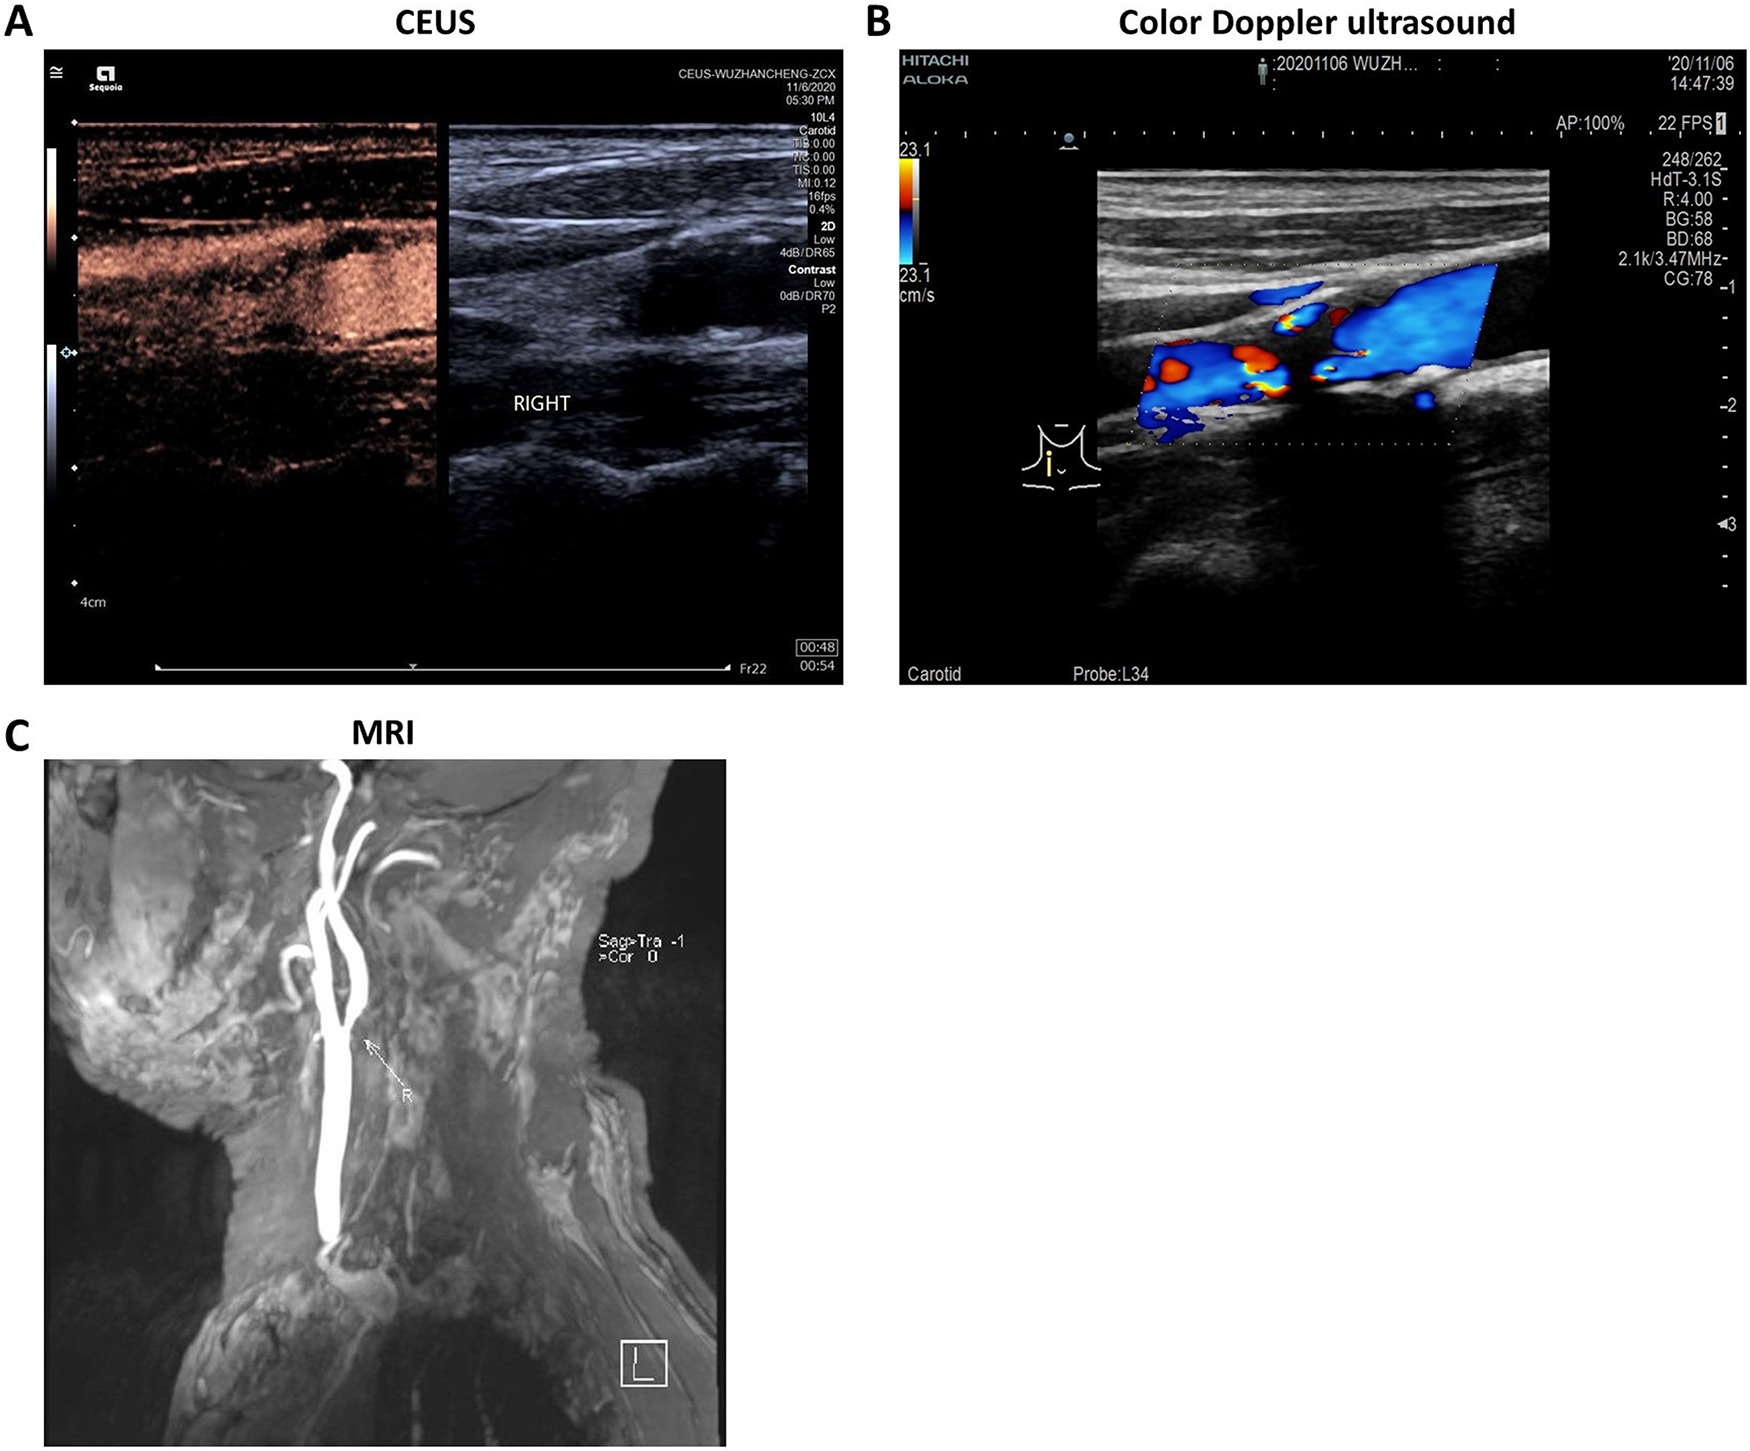

The study included a total of 517 CAS patients, with 311 (60.15%) cases of mild-moderate CAS and 206 (39.85%) cases of severe CAS. A total of 293 cases (56.67%) had stable plaques and 224 cases (43.33%) had unstable plaques. As shown in Table 1, severe CAS patients showed a significantly higher expression of CRP, IL-6, TC, and LDL-ch (all with a p-value <0.001), while the expression of HDL-ch was markedly lower in severe CAS patients (p < 0.001). Additionally, severe CAS patients showed a higher frequency of unstable plaques compared to mild-moderate patients (p < 0.001). The ratio of patients with a history of coronary heart disease was significantly higher in severe CAS patients (p = 0.008). The typical imaging results were shown in Figure 1. All the statistical calculation results for continuous data and logistic regressions are listed in the Supplementary Data (Table S1–S10).

All patients received a normal Doppler ultrasound, CEUS and MRI. The IMT was measured using an Acuson-Aspen Color Doppler ultrasound diagnostic instrument (GE Healthcare, Boston, USA) with a probe frequency of 7.5 MHz. The IMT of bilateral common carotid arteries was measured proximally and distally to the bifurcation as well as at the bifurcation. Plaques were observed and classified as stable (strong echo or medium echo) or unstable (mixed echo or low echo) plaques based on the echo condition.

Contrast-enhanced ultrasonography was used to further evaluate the conditions of the plaques using the Toshiba Aplio500 instrument (Toshiba, Tokyo, Japan) with a probe frequency of 5–14 MHz and a mechanical index (MI) of 0.08 MHz. SonoVue (Bracco, Geneva, Switzerland) was used as the contrast agent. Briefly, after the observation of the plaque, 1.0 mL of SonoVue suspension (dissolved in normal saline) was injected into a peripheral vein by rapid bolus injection, followed by an injection of 5 mL of normal saline. According to the measurement of teh plaques using CEUS, patients were described using 5 grades: grade 0 – no enhancement; grade 1 – an enhancement for adventitia but not the inner plaque; grade 2 – a small amount of scattered punctate enhancement within the plaquel; grade 3 – a linear enhancement extending into the plaque; and grade 4 – an intraplaque diffusion enhancement.

Magnetic resonance imaging was used as the gold standard to evaluate plaque conditions using a GE Discovery MR750w 3.0T MRI scanner (GE Healthcare). Briefly, after the full exposure of the neck blood vessels, the exact location of the carotid bifurcation and the plaques was obtained using 2D-TOF scanning. Then, axial scanning of the plaques was performed using T1WI, T2WI, 3D-T0F, and enhanced T1WI. For measurement of plaques, the signal-to-noise ratio (SNR) and imaging conditions were analyzed and plaques were divided into different types according to the American Heart Association (AHA) classification. Types I, II, III, VII, and VIII were considered stable while all other types were regarded as unstable.18